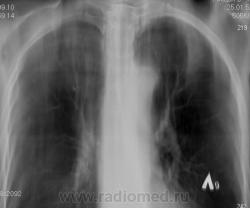

По томограммам не понятно что хотели получить? Интересовали эти маленькие плотные очаги?

Справа на верхушке инфильтративная тень. Слева в задних отделах мелкие буллы.

На последнем срезе тень в 1 сегменте, мелкие полости в верхних долях с обеих сторон.